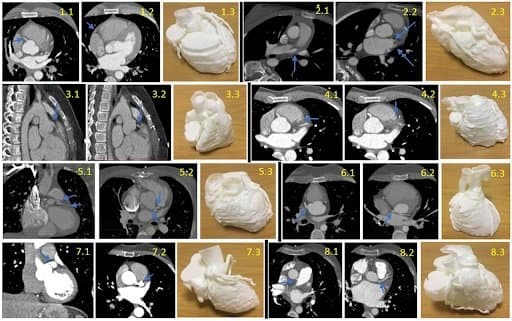

CT Scans and models of each case, with the blue arrows pointing to the abnormality on the CT.

“The CT scans, first, and then 3D-printed models were presented to groups of clinicians (n=8) and cardiovascular researchers (n=9). Models were rated according to clarity of anatomical detail, insight into the coronary abnormality, overall perceived usefulness and comparison to CT scans. Assessment of model characteristics used Likert-type questions (5-point scale from ‘strongly disagree’ to ‘strongly agree’) or a 10-point rating (from 0, lowest, to 10, highest). The questionnaire included a feedback form summarizing overall usefulness. Participants’ imaging experience (in a number of years) was also recorded.”

“Cardiac CT datasets of patients with various coronary artery anomalies (n=8) were retrospectively reviewed and processed, reconstructing detailed 3D models to be printed in-house with a desktop 3D printer (Form 2, Formlabs) using White Resin.”